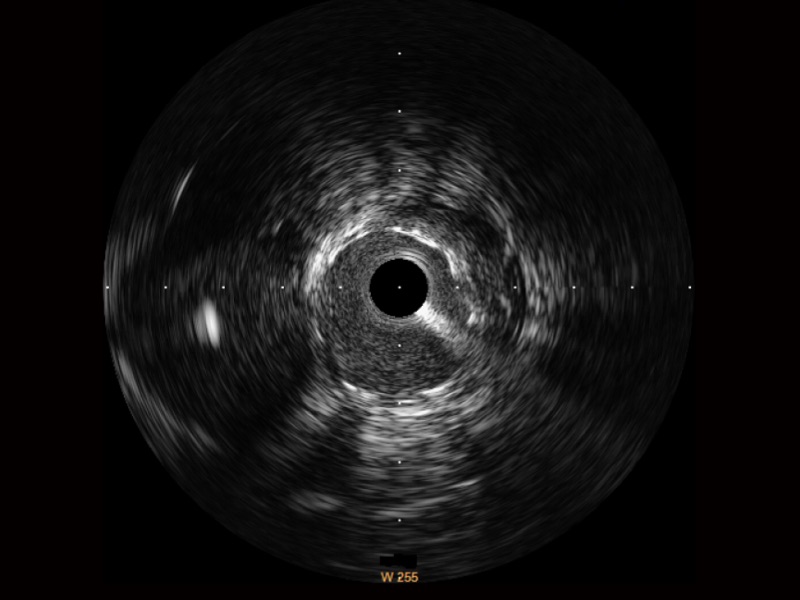

• 美狮贵宾会官网宽频IVUS图像

对比传统IVUS导管成像,美狮贵宾会官网宽频IVUS图像的近场支架梁显影更细腻,远场中膜外血管仍清晰可辨,兼顾远中近,兼顾分辨力与穿透深度